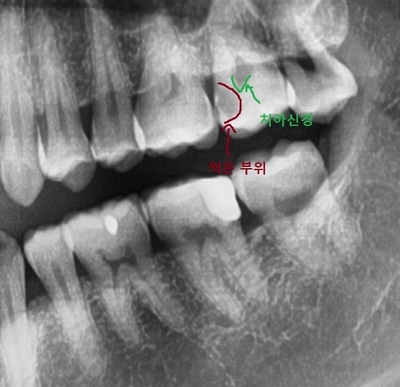

어느 치과의사가 봐도 신경과 근접하게 많이 썩은 부위가 딱! 있었습니다.

이거는 완전 신경치료+크라운 케이스...

저기 썩은 부위라고 쓰여있는 부분은 <많이많이> 썩은 부위입니다

뿐만 아니라 그 치아의 앞치아도 눈으로 봤을 때 충치가 비쳐보였습니다.

아무래도 그 두치아 사이에 음식물이 낄테고

뒷 치아가 그만큼 썩었으니

앞치아도 썩어있을 확률이 높겠죠.

"뒷치아는 신경치료& 크라운 + 앞치아는 인레이"

케이스...